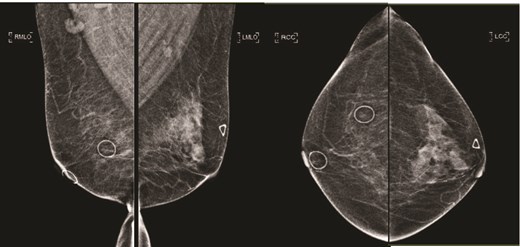

(Left) Mammography medioloateral oblique views of bilateral breasts; (Right) Mammography cranial-caudal views of bilateral breasts: Left upper central breast shows a vague focal asymmetry corresponding to the palpable concern, and several prominent right axillary lymph nodes.

(Left) Mammography cranial-caudal view of left breast; (Right) Mammography mediolateral oblique view of the left breast: Left upper outer breast spiculated mass with minimal architectural distortion.